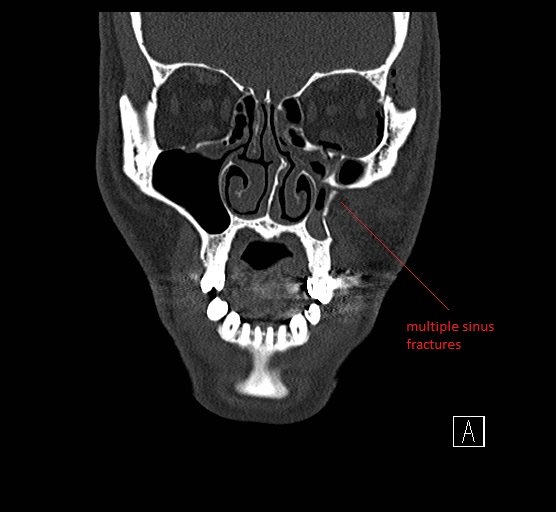

Physical exam showed marked left palpebral subcutaneous crepitus, as well as bulbar and palpebral conjunctival bulging. Visual acuity was normal with intact extraocular movements, and normal pupillary exam. Computed tomography (CT) imaging of the face was obtained and revealed multiple displaced fractures involving the left orbital floor and zygomatic arch associated with moderate periorbital and postseptal extraconal gas, resulting in orbital proptosis.